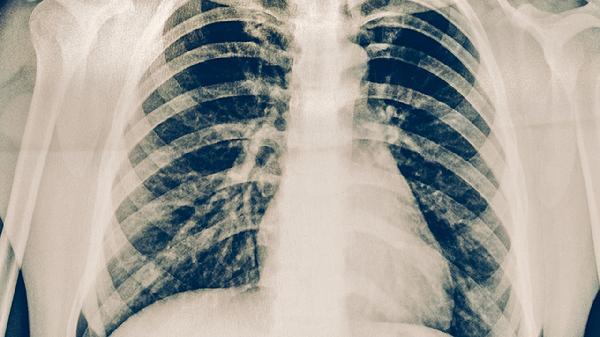

3、影像学特征

金黄色葡萄球菌肺炎胸部CT可见多发性空洞、液气平面等坏死性肺炎表现,常伴胸腔积液。化脓性链球菌性肺炎X线多显示肺段实变,少见空洞形成,胸膜受累程度较轻。